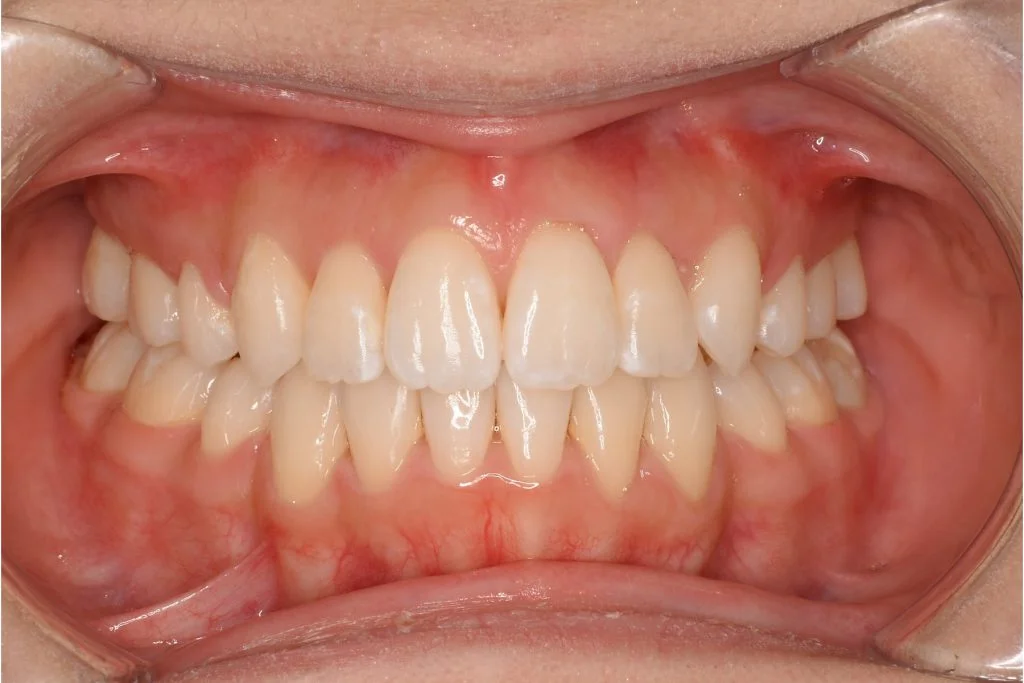

• 症例1-1治療後

治療後 マウスピース矯正のみで治療

患者さんの感想 他ではワイヤー矯正でしか治療できないと言われていたので、最初はマウスピース矯正で本当に治るのかなと少し心配でしたが、治療期間も短く、こんなに綺麗になってお願いして本当によかったです。長年コンプレックスだった歯並びが綺麗になって、以前は自分の口元を見るのが嫌でしたが、口元に自信が持てるようになり、人前で気にせず笑えるようになって人生が変わりました。